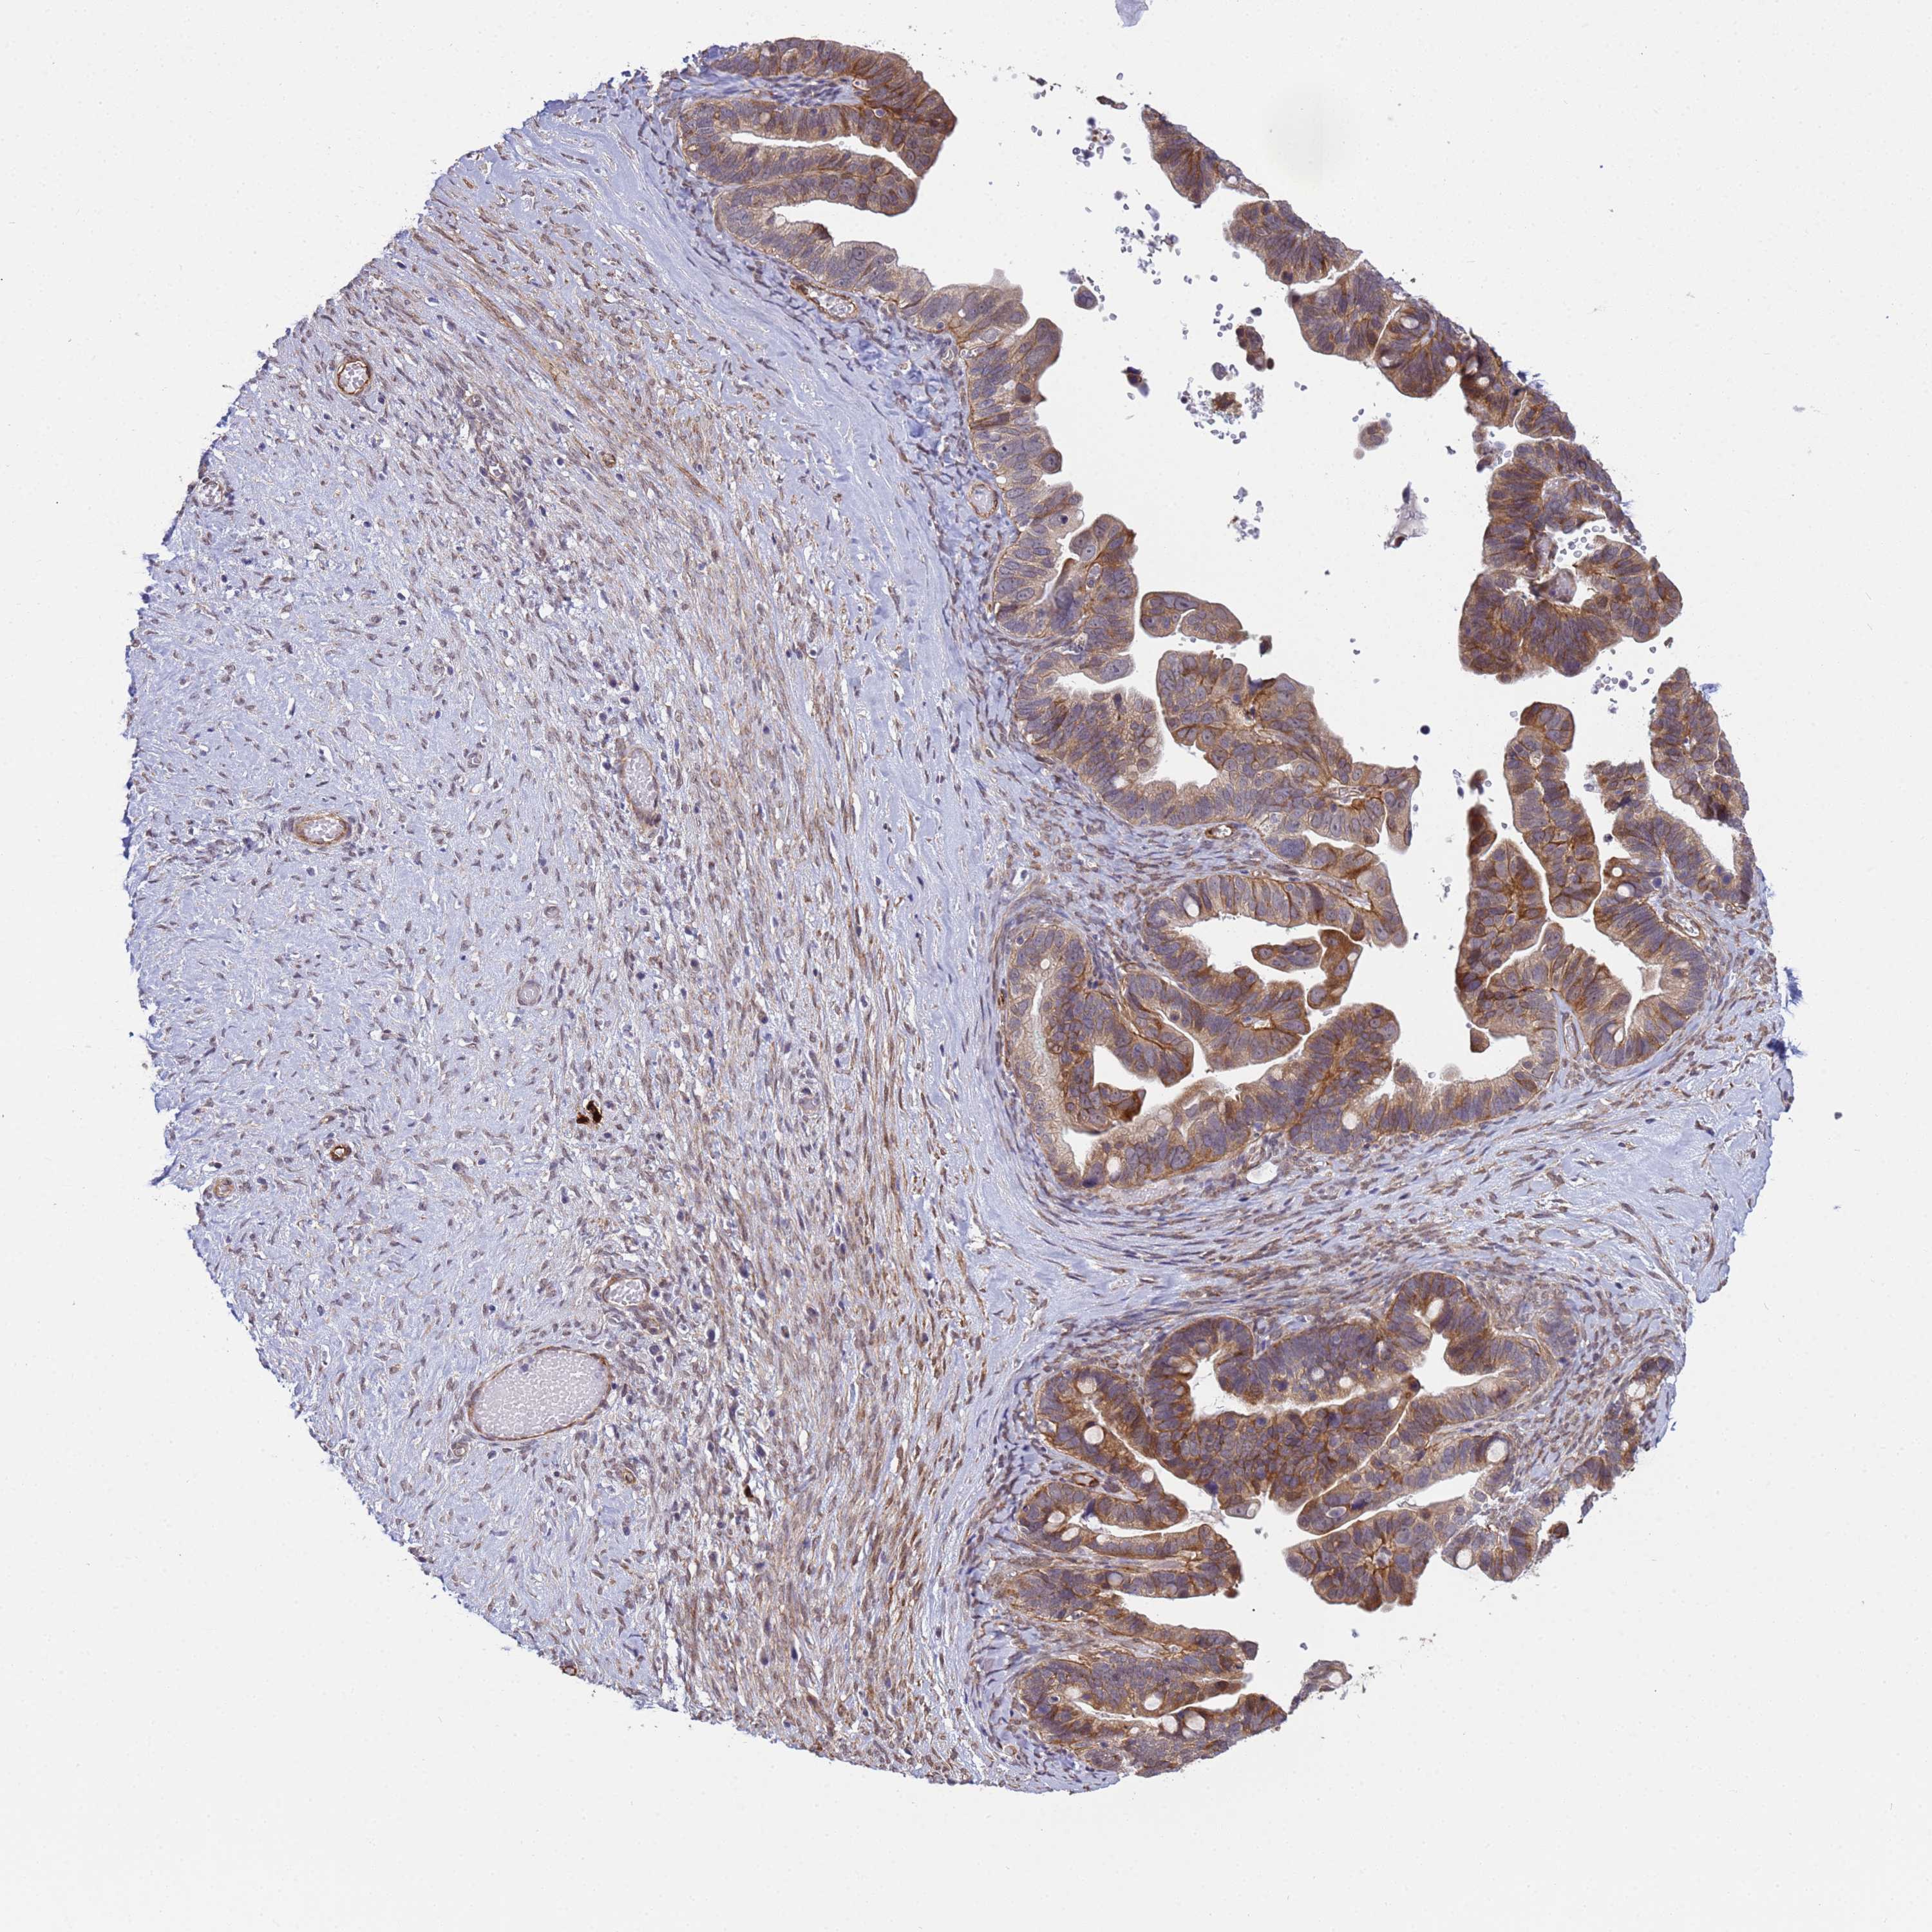

OVARIAN CANCER - Protein expressioni

A mouse-over function shows sample information and annotation data. Click on an image to view it in a full screen mode. Samples can be filtered based on level of antibody staining by selecting one or several of the following categories: high, medium, low and not detected. The assay and annotation is described here.

Note that samples used for immunohistochemistry by the Human Protein Atlas do not correspond to samples in the TCGA dataset.

Antibody stainingi

Antibody staining in the annotated cell types in the current human tissue is reported as not detected, low, medium, or high, based on conventional immunohistochemistry profiling in selected tissues. This score is based on the combination of the staining intensity and fraction of stained cells.

Each image is clickable and will lead to virtual microscopy that enables deeper exploration of all samples and also displays staining intensity scores, fraction scores and subcellular localization as well as patient and tissue information for each sample.

Antibody HPA036348

Antibody HPA036349

Antibody CAB002422

Antibody CAB005258

Cystadenocarcinoma, serous, NOS

Carcinoma, NOS

Cystadenocarcinoma, mucinous, NOS

Carcinoma, endometroid